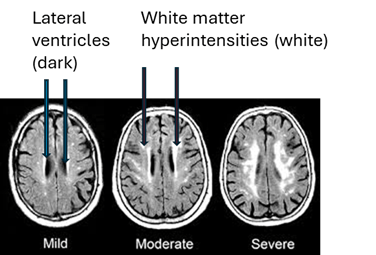

The three groups of participants were compared with regard to the size, number and location of any “white matter hyperintensities” (WMHs), examples of which appear in the MRIs below as the irregular white dots and splotches. In mild form, they’re common in healthy, older people and more so in those with high blood pressure, diabetes and other vascular risk factors. You can see how some of them sit smack up against the black slits in the middle of the brain, the spinal-fluid-filled lateral ventricles, and some are much closer to the outer, convoluted surfaces of the brain, the cerebral cortex. (Image from Inzitari D, Pracucci G, Poggesi, et al. BMJ. 2009 Jul 6;339:b2477. doi: 10.1136/bmj.b2477